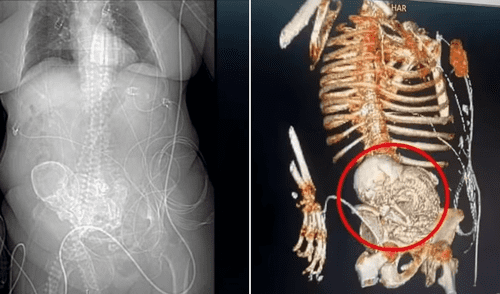

Una mujer de 81 años de Brasil falleció luego de una cirugía para extraer un feto calcificado. Este feto estuvo en su cuerpo por más de treinta años. El caso ocurrió en el Hospital Regional Dr. José de Simone Netto, en el estado de Mato Grosso do Sul. Este evento generó gran impacto, pues la condición médica es poco común. Se le conoce como litopedia o “bebé de piedra”.

La paciente, identificada como Daniela Vera y presentaba una infección abdominal severa y, durante las evaluaciones médicas, se descubrió el feto calcificado en su cavidad abdominal. Aunque la cirugía logró extraer el cuerpo extraño, la mujer falleció al día siguiente a causa de complicaciones médicas.

El equipo médico decidió intervenir de emergencia para controlar la infección, la cual se sospechaba relacionada con la presencia del feto calcificado. La mujer fue hospitalizada el 14 de marzo de 2024 después de sufrir una caída y operada el 15 de marzo. La cirugía permitió extraer con éxito el “bebé de piedra”. Sin embargo, el estado de salud de la paciente ya era crítico y, pese a los esfuerzos del personal médico, falleció al día siguiente.

La litopedia es una condición médica excepcional en la que un feto muere durante un embarazo ectópico abdominal es decir, fuera del útero, y no puede ser reabsorbido por el cuerpo. Ante esta situación, el organismo lo encapsula con capas de calcio como mecanismo de defensa para evitar infecciones.

El término, de origen griego, significa literalmente “bebé de piedra”. Se han documentado menos de 300 casos en todo el mundo. La condición puede pasar desapercibida durante años si no hay síntomas notorios o si la persona evita acudir a controles médicos. En algunos casos, el feto puede permanecer décadas sin ser detectado.